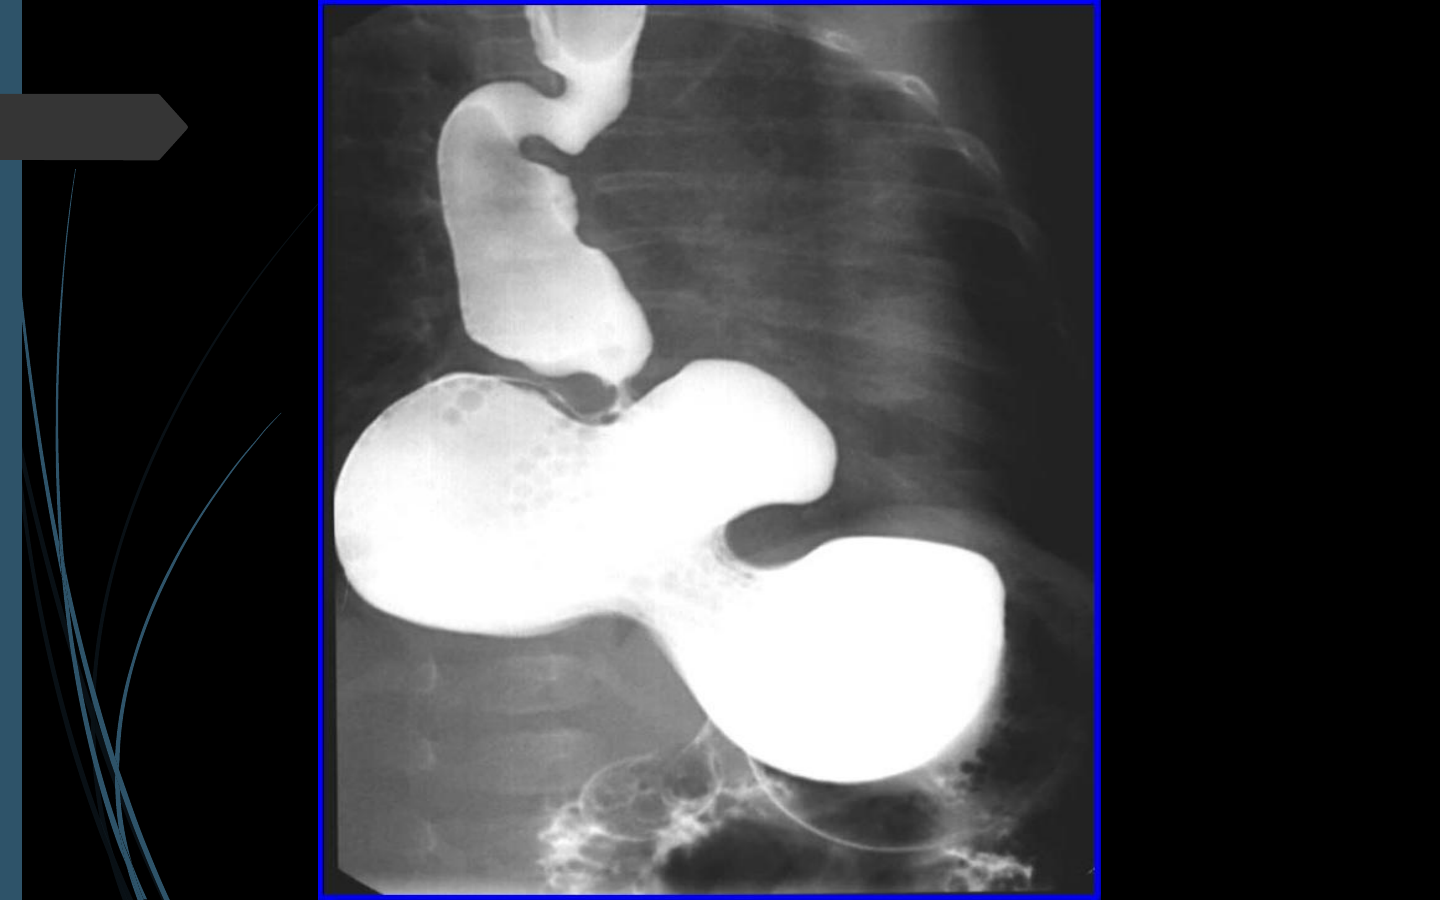

Causesœsophagiennes:àrechercherenpremier

(œsophagite,RGO,dyskinésieœsophagienne…)